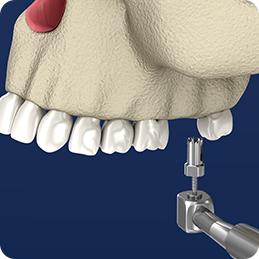

step 01골 이식 입구 생성치아 뿌리 방향으로 이식재가 들어갈 구멍을 뚫습니다.

step 02상악동 공간생성상악동의 점막을 들어올리고 뼈이식을 진행할 공간을 만들어줍니다.

step 03골 이식재 충전만들어진 상악동 공간에 이식재를 충전해줍니다.

step 04상악동 공간생성상태에 따라 거상술과 함께 임플란트를 식립하거나 골이식 후 임플란트를 식립합니다.